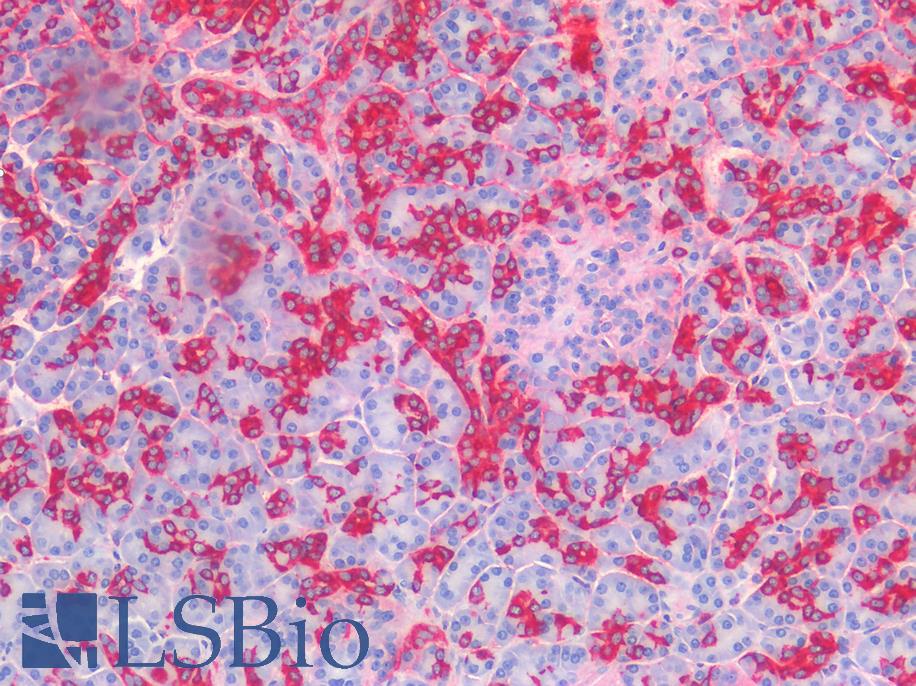

PD1 (PDCD1 / CD279)

Anti-CD279 / PD-1 antibody IHC of human tonsil. Immunohistochemistry of formalin-fixed, paraffin-embedded tissue after heat-induced antigen retrieval. Antibody LS-B7883 dilution 20 ug/ml.